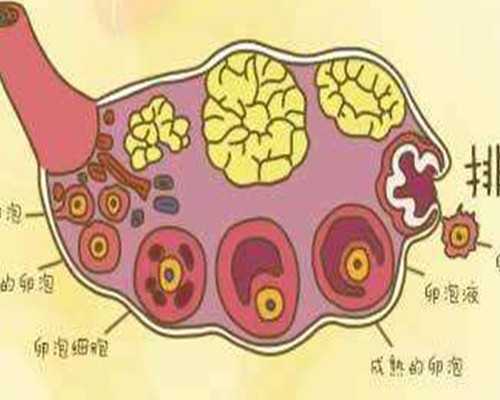

不同年齡階段的女性做試管嬰兒,其用藥量也會不一樣。由于,隨著女性年齡的增長,卵巢功用逐步衰退,所以在做試管嬰兒時,年齡偏大的女性用藥量會相對較多,進而增加了相應的費用。

5、選對促排方案

不同促排卵計劃用藥品種及用藥量不同。相比而言,微刺激計劃、自然周期計劃、黃體期計劃由于用藥較少,因而要求的治療費和藥費低于其他計劃。試管嬰兒醫院關于排卵計劃的制定一定是依據就診者目前的身體狀況,選擇有利的計劃進行。